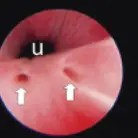

Urinary Endoscopy

An experienced endoscopist can usually identify EUs (Figure 3, arrows; U = urethra lumen).

(Photo courtesy of Dr. John Kruger, Michigan State University)